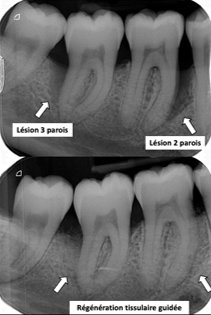

- Radiographies très précises évaluant les supports osseux autour des dents.

Si le traitement de surfaçage n’a pas été suffisant, une étape parfois chirurgicale sera nécessaire sur certaines dents pour éliminer les tissus infectées sous la gencive en soulevant chirurgicalement la gencive.

Parfois, même si la maladie parodontale est stabilisée, certains sites autour des dents peuvent bénéficier d’une régénération osseuse par la mise en place de biomatériaux dans le défaut ce qui permet de renforcer la dent et revenir à une situation presque normale.